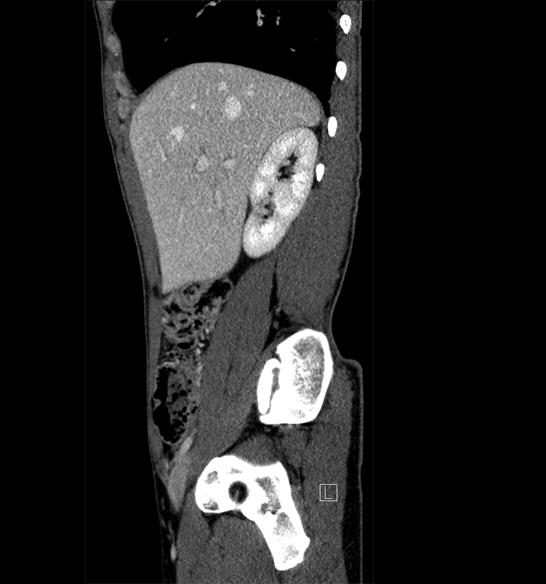

Body

Covers abdominal CT anatomy.